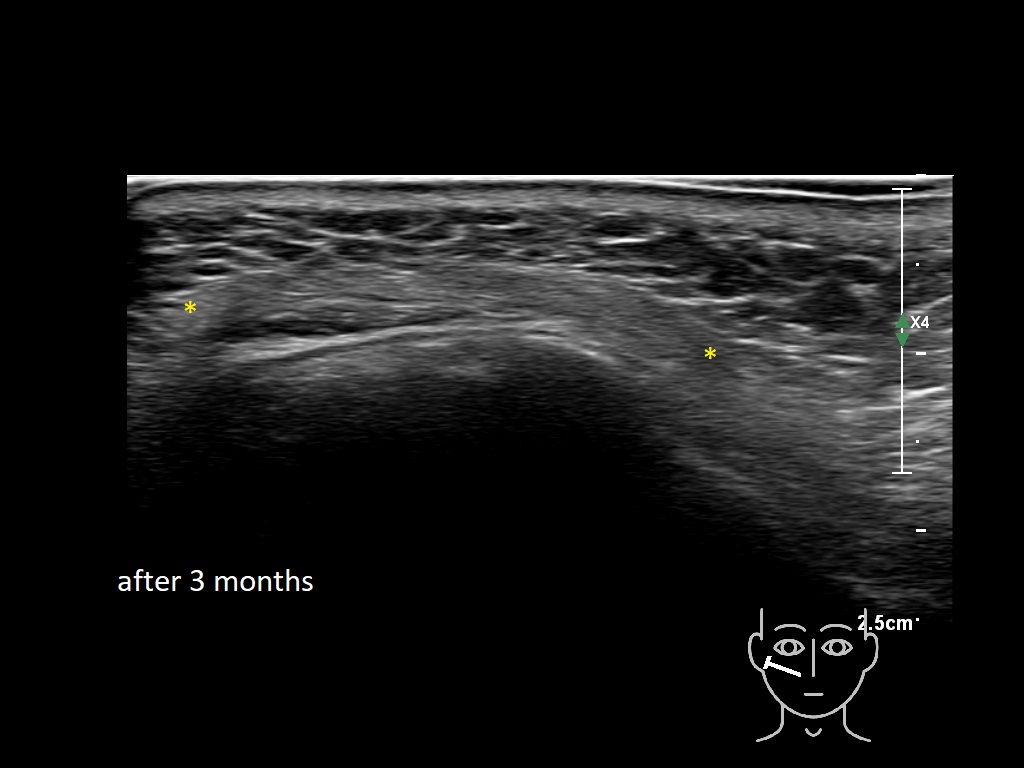

Draw in the image on the right where the fillers are located. To check if your answer is correct, please click on the secondary image.

Draw in the second image below where the fillers are located. To check if your answer is correct, swipe the first image to the right.